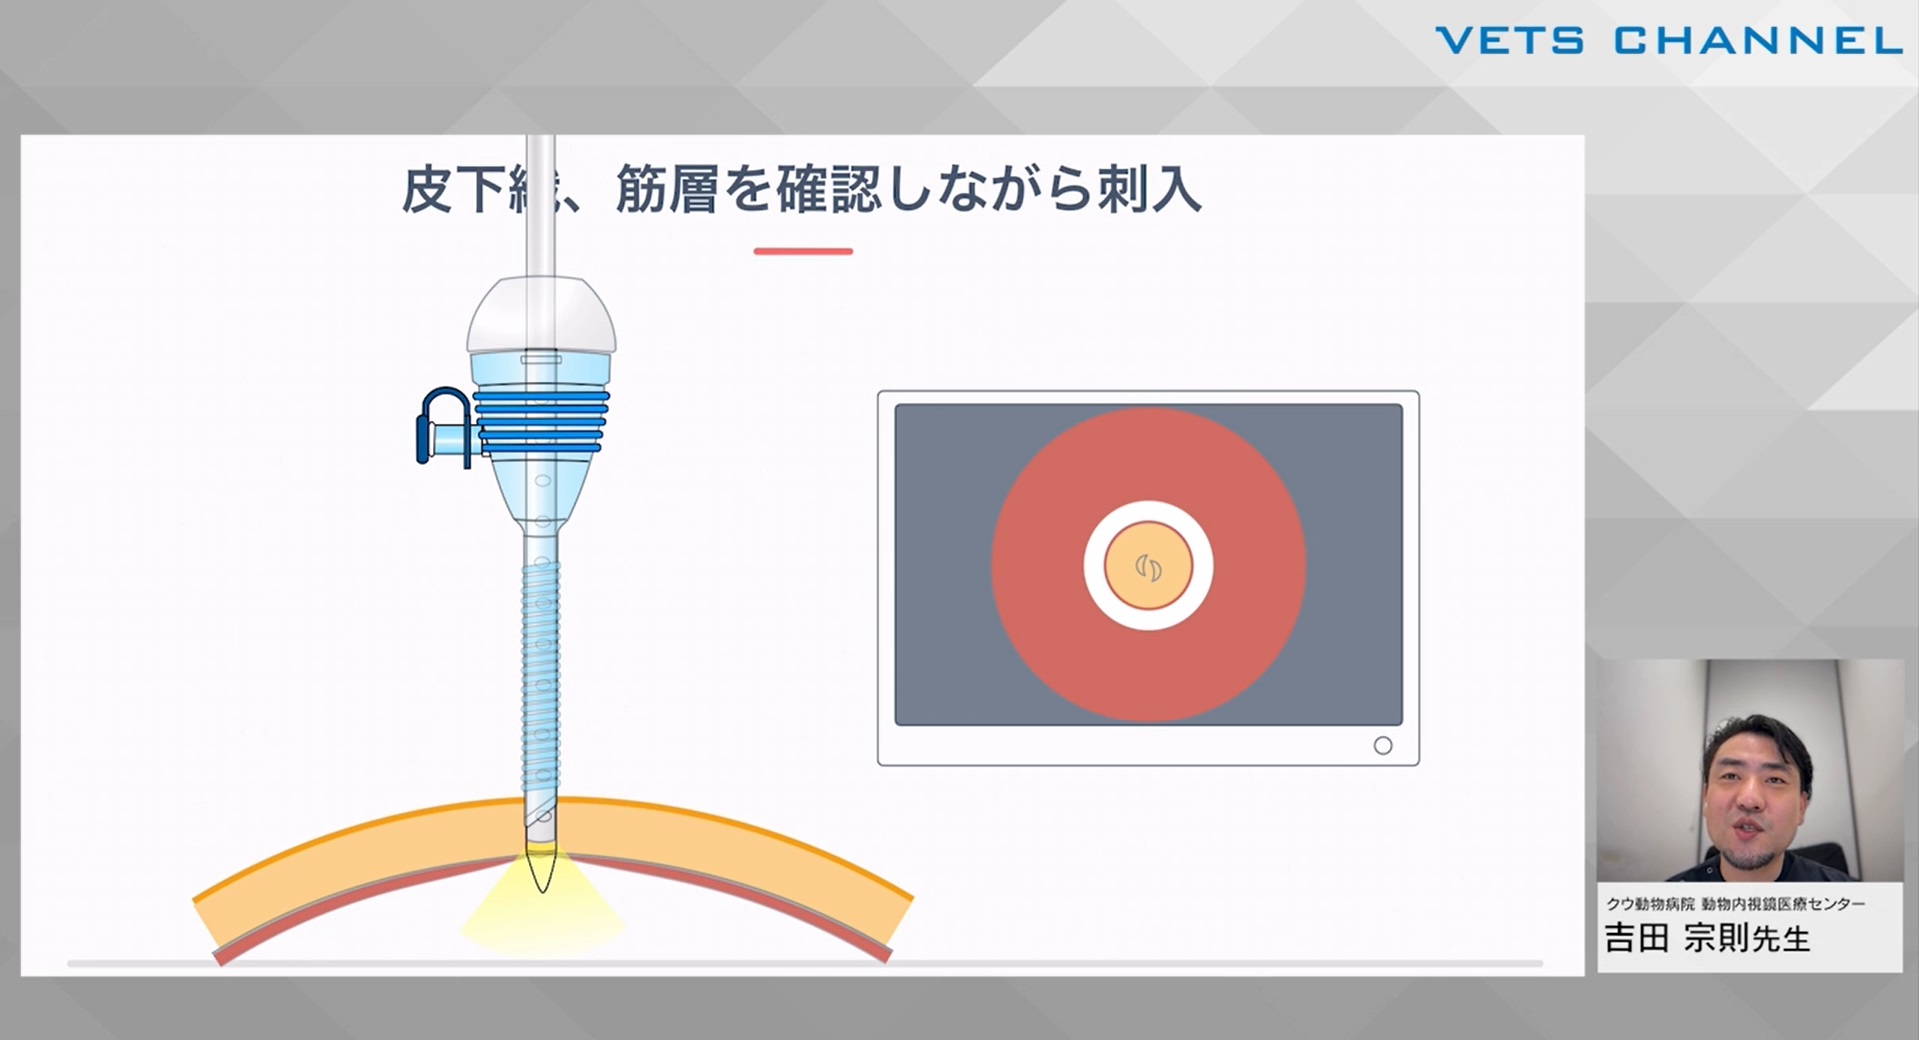

初学者のための腹腔鏡テクニック 第4回:「円滑な手術を実施するために」

- テクニック

- 内視鏡科

吉田 宗則先生(クウ動物病院 動物内視鏡医療センター)

46分

2025/01/03

初学者のための腹腔鏡テクニック 第3回:「トロッカーと気腹」

- テクニック

- 内視鏡科

吉田 宗則先生(クウ動物病院 動物内視鏡医療センター)

60分

2025/01/03

初学者のための腹腔鏡テクニック 第2回:「手術計画と準備」

- テクニック

- 内視鏡科

- 特殊器具が必要

吉田 宗則先生(クウ動物病院 動物内視鏡医療センター)

54分

2025/01/03

初学者のための腹腔鏡テクニック 第1回:「腹腔鏡手術を始める前に」

- テクニック

- 内視鏡科

- 特殊器具が必要

吉田 宗則先生(クウ動物病院 動物内視鏡医療センター)

60分

2025/01/03